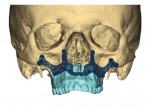

Virtual surgical planning in this case is demonstrated in Figure 6 through Figure 9: preoperative 3D CT imaging and planned surgical bony changes (Figure 6), preoperative 3D CT imaging and planned surgical soft-tissue changes (Figure 7), and examples of prefabricated cutting guides (Figure 8) and plates/screws for the maxilla (Figure 9). Careful attention must be paid to the root apices of the upper posterior and lower anterior teeth, the position of the inferior alveolar nerve and mental foramen, and any potential bony interferences after the reposition of the maxilla and mandible.

Once a stable, reproducible final occlusion is confirmed, attention is turned to the genial tubercle advancement. This is a small, 1 cm x 2 cm bony block extending from just inferior to the anterior mandibular tooth roots that allows for the advancement of the genioglossus musculature and thus the tongue, resulting in greater posterior airway space (usually 6 mm to 8 mm). In the present case, the advancement of the genioglossal attachments was 6 mm (Figure 12).